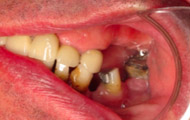

Exemple d’une réhabilitation complète implantaire

Situation clinique initiale

Situation clinique terminée